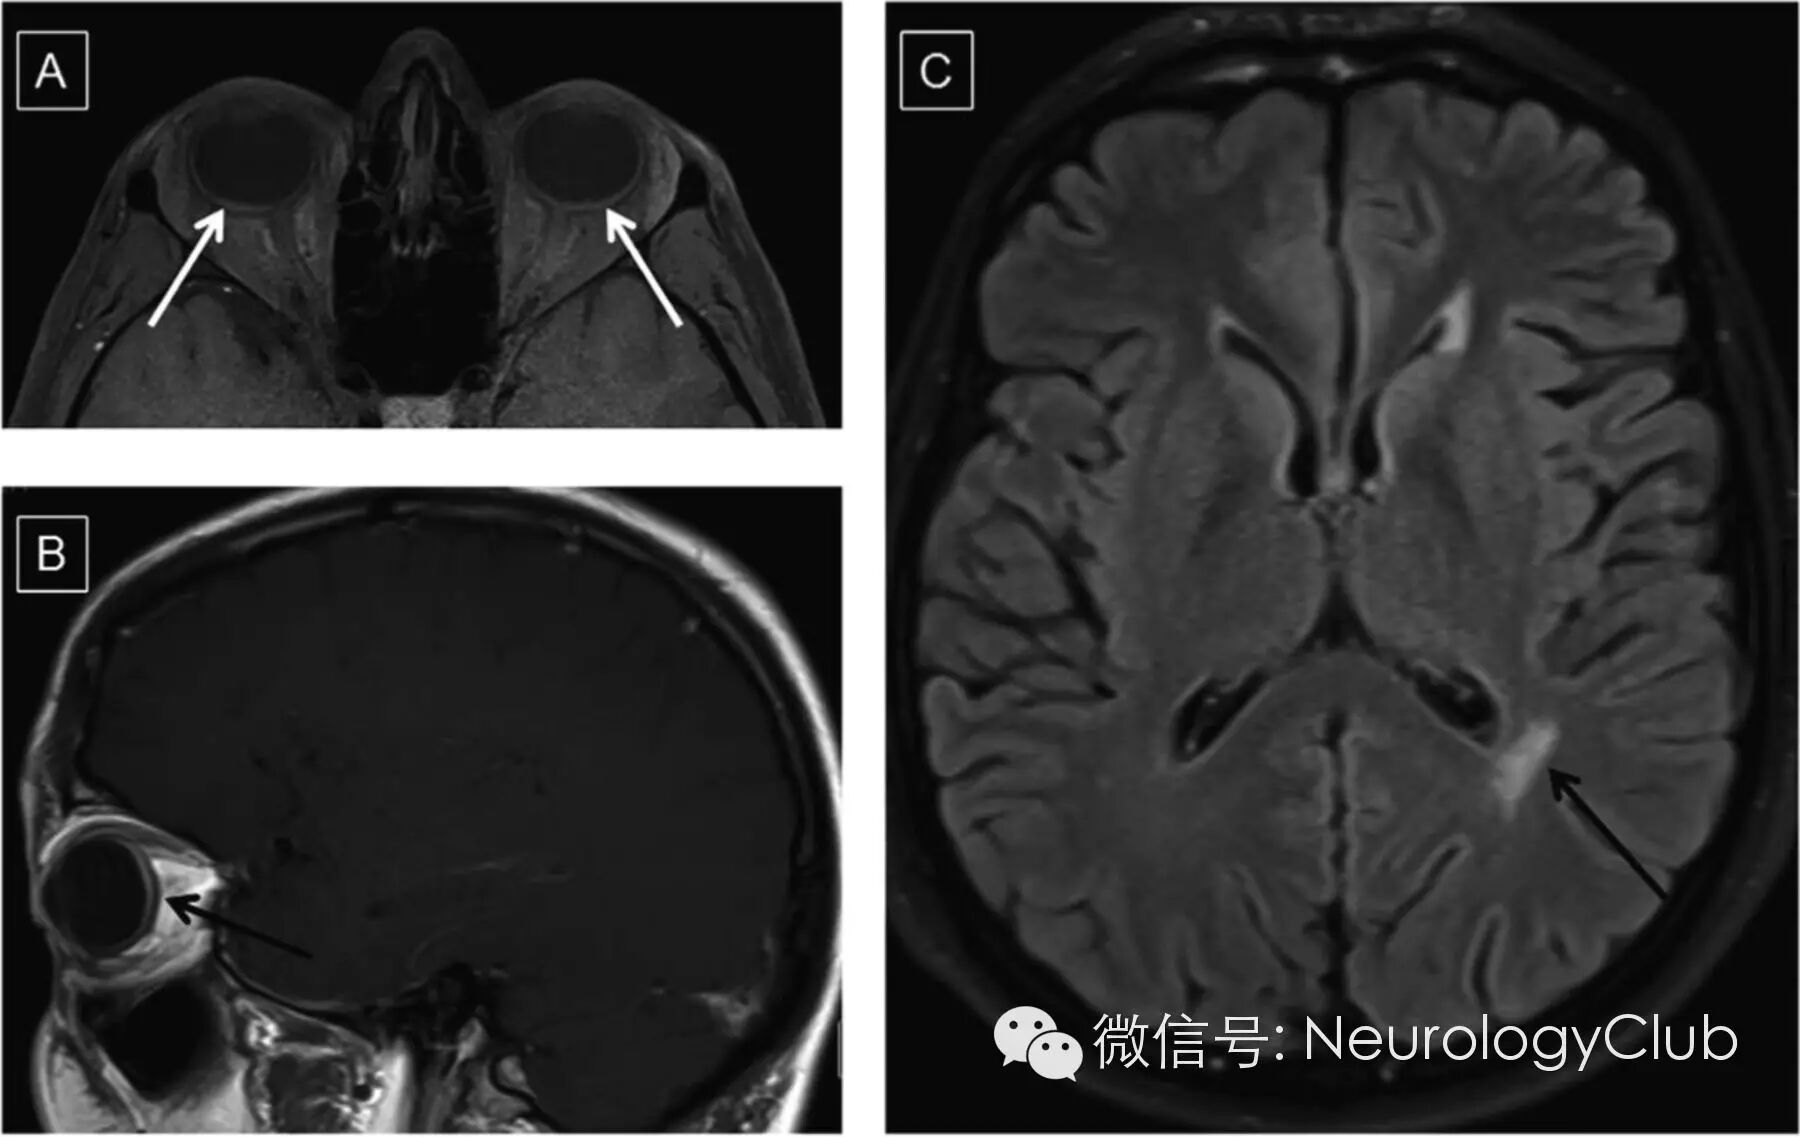

(A-B:T1WI可见对称的脉络膜增厚伴视网膜脱离;C:FLAIR提示侧脑室旁白质高信号病灶)